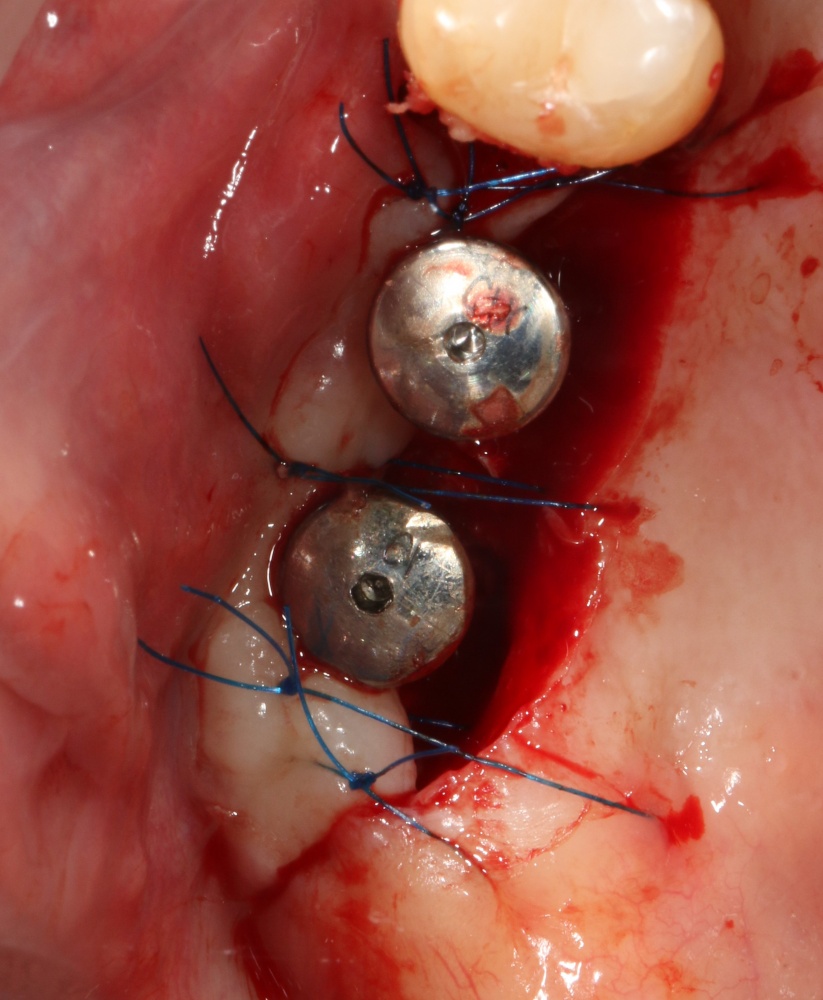

Следующая задача — найти импланты, которые полностью заросли костной тканью:

Ставим на них формирователи десны, ушиваем рану с расчетом на вторичное натяжение.

Здесь важно предупредить пациента о возможном сильном кровотечении. Иногда бывает.

Далее, нам остается герметизировать послеоперационную рану тщательным и аккуратным наложением швов. Напомню, как разрезы, так и швы делаются в пределах кератинизированной слизистой оболочки. Это позволит уберечь рану от расхождения краев.

Послеоперационное ведение включает в себя периодические осмотры, антибактериальную и противовоспалительную терапию, некоторые правила послеоперационного режима на период 3-7 дней. Швы снимаются на 12-14 день, после чего ждем 3-4 месяца до момента регенерации костной ткани и интеграции имплантов.